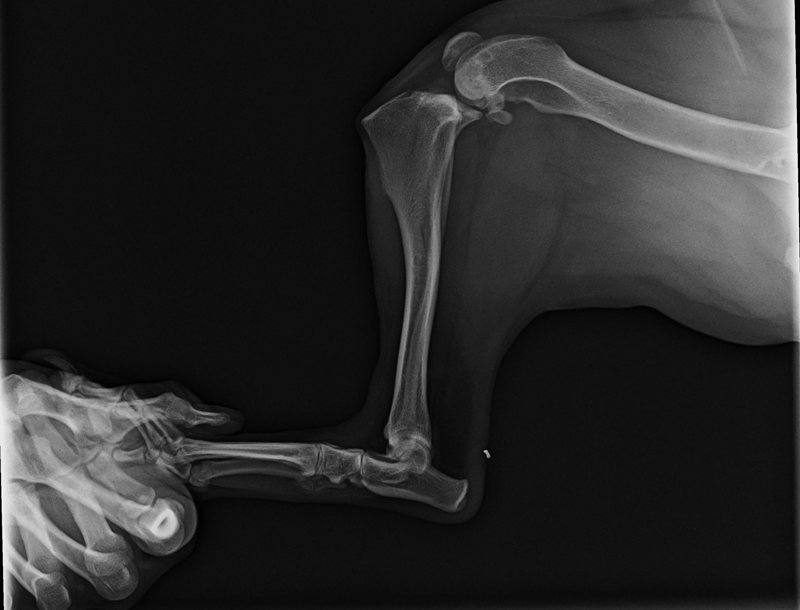

2015 X-Ray Contest WinnersAugust 31, 2015Every year for the past decade, Veterinary Practice News has hosted the annual “They Ate What?!” competition, where veterinarians send in the most eye-popping radiographs their practices have encountered. In past years, our judges have seen plenty of balls in bellies. But not 26 golf balls in one Dobie belly. The radiograph and corresponding photo won first place for Gordon Schmucker, DVM, of Lisbon Veterinary Clinic in Lisbon, Ohio. This year’s contest was sponsored by Trupanion pet insurance of Seattle. The Veterinary Practice News editorial team judged the entries. First prize received $1,500; second, $1,000; and third, $500. Mike Jones, DVM, of Woodland West Animal Hospital in Tulsa, Okla., won second place with his 10-week old Labrador, who had ingested the end of a fishing pole. Theresa Taylor, DVM, of Cherryville Animal Hospital in Cherryville, N.C., won third place. Her radiograph found a door hinge in a 6-month-old Lab. “Foreign body ingestions are among the most common high-dollar claims we cover,” said Steve Weinrauch, BVMS, MRCVS, Trupanion’s chief veterinary officer. "It’s our second most common claim for dogs and third most …